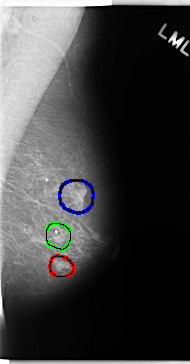

C_0157_1.RIGHT_MLO

FILE: C_0157_1.LEFT_MLO.OVERLAY

TOTAL_ABNORMALITIES 3

ABNORMALITY 1

LESION_TYPE MASS SHAPE OVAL MARGINS MICROLOBULATED

ASSESSMENT 4

SUBTLETY 5

PATHOLOGY MALIGNANT

TOTAL_OUTLINES 1

ABNORMALITY 2

ABNORMALITY 3